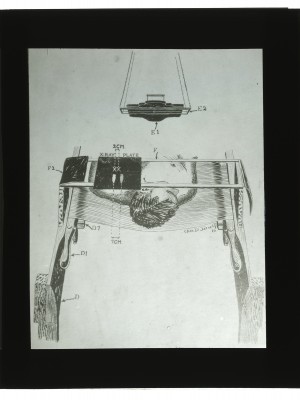

Dr. Edwin Ernst, an only child born to St. Louis residents Charles and Catherine Ernst, was a notable Roentgenologist, a physician who specializes in radiological work. Dr. Ernst studied at Washington University in St. Louis and later at Moravian College in Bethlehem, Pennsylvania earning his advanced degrees. For two years he served as a resident physician at the St. Louis Mullanphy Hospital before leaving to pursue a private practice. When the United States formally entered the war in 1917, Ernst left St. Louis to become chief radiologist at Base Hospital 21. He was discharged honorably in 1919 with the citation of Major. His collection consist of x-ray images taken at Base Hospital 21 as well as drawings of radiological equipment and photographs.